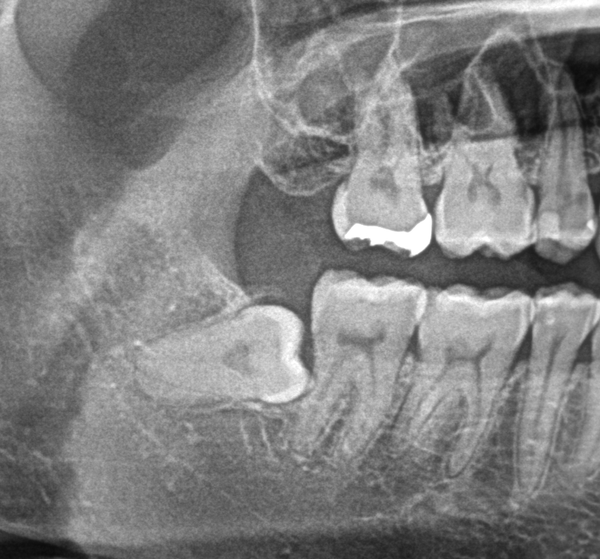

実際には、右上歯に関しては癒合歯といわれる2番目の歯と3番目の歯がくっついてしまっている状態で、サイズも通常より大きく形態も通常とは異なり変色もしていました。

まっすぐ生えてしっかりとかみ合っている場合もあれば、斜めに生えている場合もあり、顎の骨の中に埋まっている場合もあります。

すべてのケースで抜歯が必要なわけではありませんが、汚れがたまりやすく、虫歯になる場合が多くあります。また、ブラシがきれいに当たらず歯茎周りに汚れが残りやすく、歯茎が腫れて痛みが出る場合も多くあります。

例として矮小歯、癒着歯、癒合歯などが代表的なものです。これらの原因は胎児の頃にまで遡ります。完全な原因は特定できませんが、偶発的に発生するものとされており、問題がなければ通常は歯科医院での定期的な検診で経過観察をしていく事が多いです。

今回の場合では、2本の歯が1本に癒合している状況であり、変色もあったため、被せ物の治療を行うことになりました。